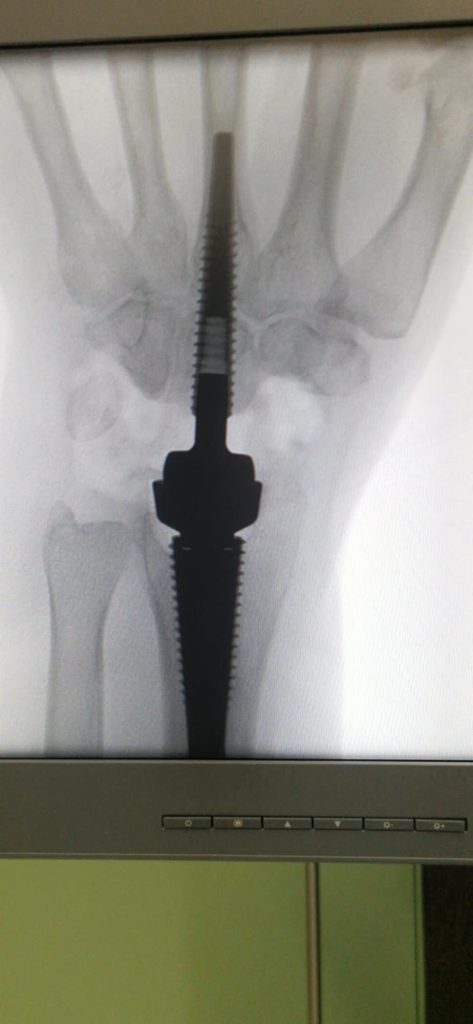

Uporabljena večkomponentna proteza je na tržišču razmeroma nova, vendar izjemno učinkovita. Med operacijo kirurgi odstranijo obrabljene zapestne kosti, pripravijo natančno ležišče v dlančnici in koželjnici ter vanju vstavijo stabilno protezo, pri čemer se celoten potek nadzira z rentgenskimi posnetki. Operacija traja približno uro in pol, poteka pa lahko v regionalni ali splošni anesteziji.